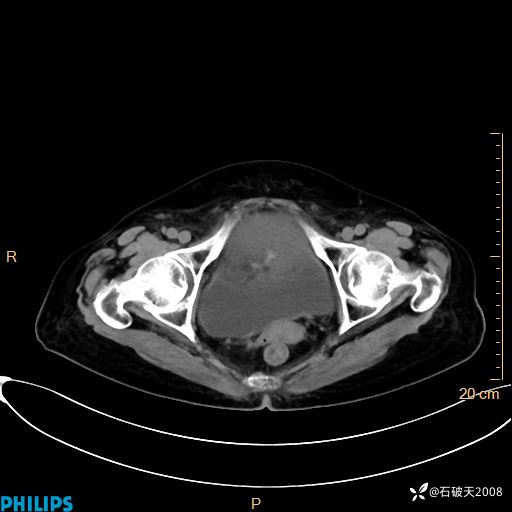

静脉期